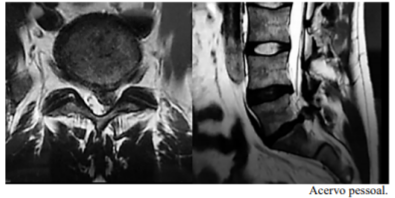

Um paciente de 46 anos de idade, com 82 kg, procura atendimento de urgência por causa de lombociatalgia à esquerda, iniciada pela manhã após esforço físico (o paciente é trabalhador braçal). Relata dificuldade para deambular desde então, principalmente em razão de dor em perna e calcâneo esquerdos. Nega alteração de sensibilidade ou de controle de esfíncteres. Relata lombalgia crônica, porém nega episódios de crises como o atual. Nega outras queixas e alergias. Ao exame neurológico, verificaram-se motricidade, sensibilidade e reflexos aparentemente preservados limitação da mobilização em MIE pelo quadro álgico, Lasegue positivo a 15 graus à esquerda. O paciente refere dor discreta à palpação da musculatura paravertebral e realizou a ressonância magnética (RM) da coluna lombossacra, conforme se observa na imagem.

Uma radiografia funcional/dinâmica da coluna lombossacra pode ajudar a decidir o plano cirúrgico desse paciente, caso seja indicado cirurgia.